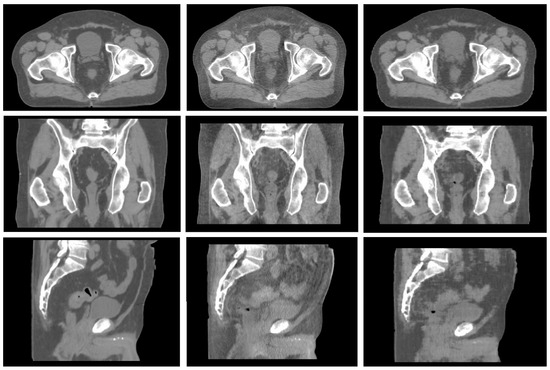

As for PTV percentage metrics, a mean percentage difference of 0.4 ± 0.3% was observed in the estimation of V95% [%] and 0.2 ± 0.1% in the estimation of V105% [%]. All the DVH indicators related to dose values were in agreement within 1 Gy between the calculations on CT and sCT. Figure 4 reports the axial dose distribution obtained on a palliative case as calculated on the real CT (left) and on the synthetic CT (right).

Figure 4. Visual representation of dose axial dose distribution obtained on a palliative case as calculated on the real CT (left) and on the synthetic CT (right).